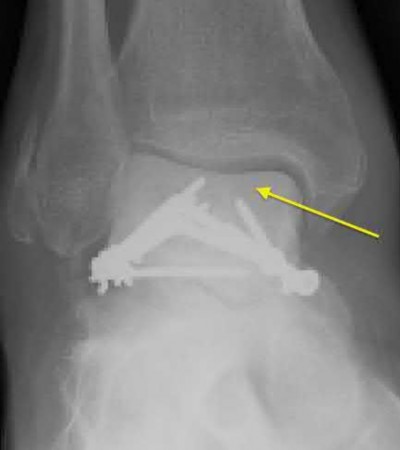

A 25-year-old male sustains an ankle fracture dislocation and undergoes open reduction and internal fixation. He returns to clinic five months following surgery complaining of continued ankle pain and instability with weight bearing. His immediate post-operative AP radiograph is seen in Figure A. Which of the following could have prevented this patient from developing persistent pain?

The patient presents with continued ankle pain and instability following open reduction and internal fixation. The radiograph in figure A demonstrates inadequate restoration of fibular length, likely leading to continued tibiotalar instability.